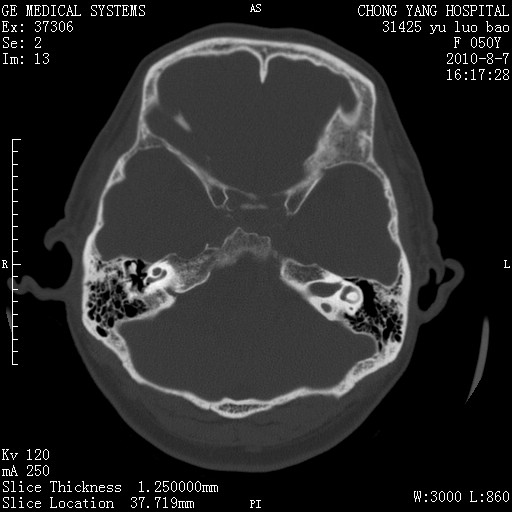

骨窗示右侧内听道扩大,考虑右侧听神经瘤。

右侧桥小脑角去等密度占位,右侧内听道扩大、骨质吸收,考虑:右侧听神经瘤,建议增强检查。

右侧内听道扩大、骨质吸收,中脑受压左移,考虑:右侧听神经瘤,建议增强检查。支持!

右侧桥小脑角区等密度占位,内耳道扩大,听神经瘤